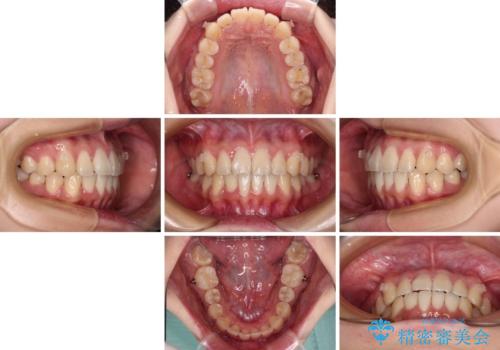

しっかりと装着時間を守ってくださったので、予定通り1年強で治療を終えることができました。